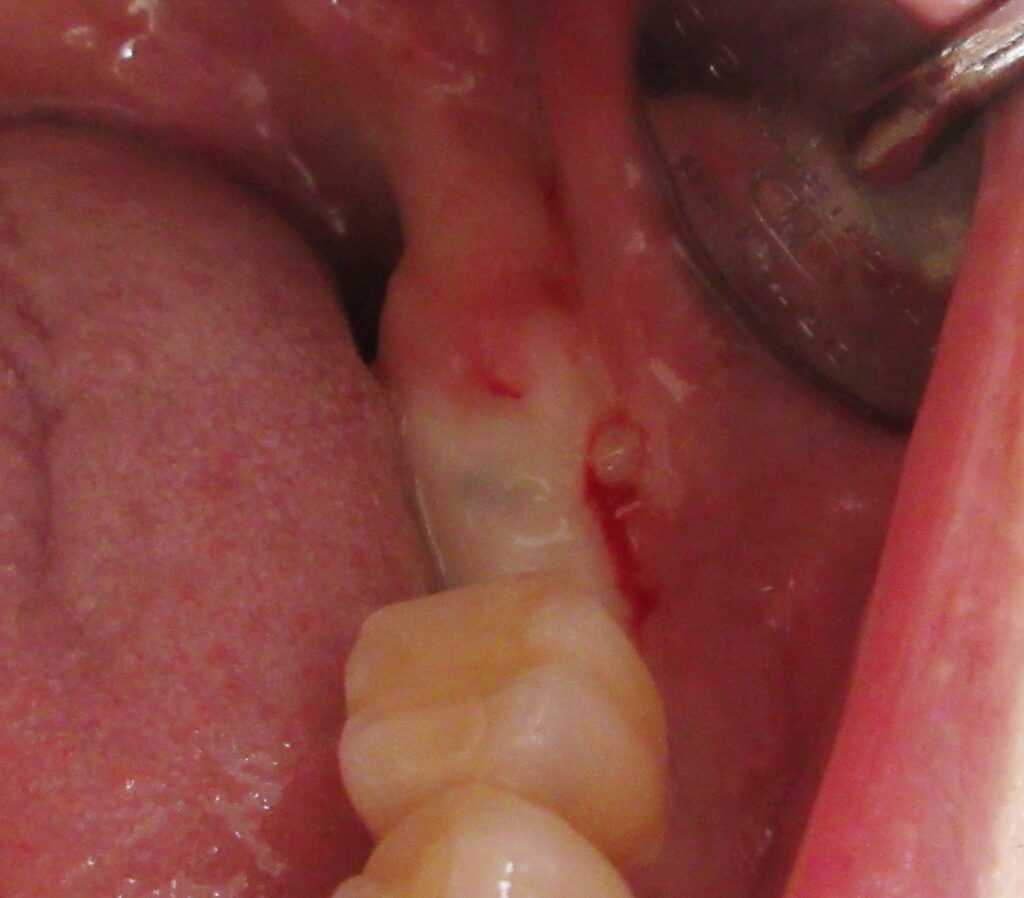

麻酔が効いている事が確認されると、すぐにオペ開始です。

左下7番目の歯茎から骨の部分までを穴開けパンチの要領で穴を開けていきます。

くりぬいた部分の歯肉を取り除き、次は骨に穴を開けていきます。